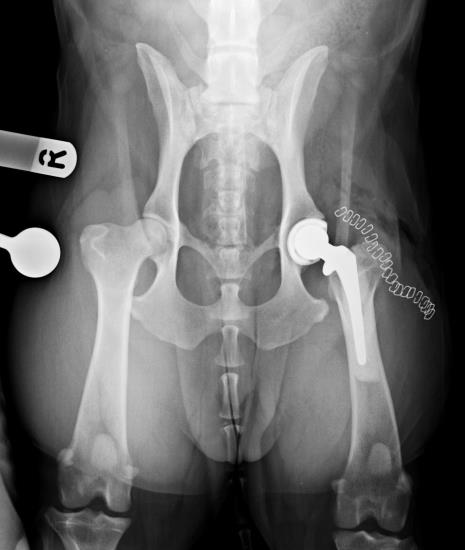

Total hip replacement at Eastcott Referrals Swindon

During the last 5 years, we have developed a well-established total hip replacement programme at Eastcott Referrals using the Biomedtrix Universal Hip system. We are able to offer this life-enhancing surgery to a wide range of patients from cats and toy dogs to giant breed dogs. Total hip replacement is an extremely effective treatment for a variety of conditions affecting the hip including hip dysplasia, osteoarthritis, failed femoral head and neck excision, complex femoral head fractures or femoral head necrosis (Legg-Calve-Perthes disease). We are always keen to see potential cases early on in the progress of disease. This allows us to discuss all the options for treatment, the expected outcomes and potential complications that could be encountered. We believe that it is important to ensure that owners are thoroughly counselled prior to embarking on surgery and will usually recommend an initial course of aggressive conservative treatment. If successful, this can allow surgery to be avoided or postponed, but will also optimise the physical condition of animals which do go on to have total hip replacement. Surgery is performed by our experienced orthopaedic team led by RCVS Recognised Specialist in Orthopaedic Surgery, Duncan Barnes. We are happy to discuss any potential cases with you prior to referral by phone or email.